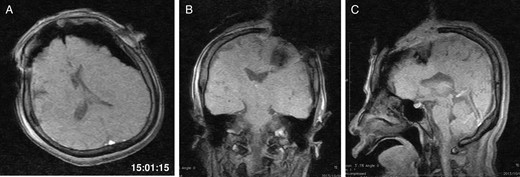

General anaesthesia was induced. Following left frontal craniotomy and dural incision, the first iMRI was performed (Fig. 1 ). One hundred fifty-eight minutes from induction, the patient regained consciousness after all anaesthetics were ceased. Tumour resection was performed with free conversation. However, after 143 min of surgery under the awake condition, the patient came to complain of excessive sleepiness though she could respond to verbal commands. Electrocorticogram (ECoG) did not detect after-discharge. The tumour was successfully removed en bloc fashion. Progressive brain swelling was not observed. The second iMRI was commenced 182 min into the awake phase (Fig. 2). Thirteen minutes from the beginning of the second iMRI scanning, the patient did not respond to noxious stimuli. When the patient was removed from the gantry, she was unconscious and had stopped spontaneous breathing. Her pupils were isocoria and did not dilate. Neither epileptic seizure nor anaphylactic reaction occurred. The peripheral oxygen saturation was not measurable, but cardiac instability or signs of vomiting were not observed. We decided to discontinue the operation under the awake status. No electrolyte imbalance or hypoglycaemia was observed. Subsequently performed iMRI identified a thin subdural haematoma in the contralateral side (Fig. 3). The fourth iMRI confirmed that most of the haematoma was evacuated following right frontal craniotomy.

The first intraoperative magnetic resonance images performed after the craniotomy. (A) Axial, (B) coronal and (C) sagittal T1-weighted scout images show the left frontal tumour. The time of scan is superimposed.